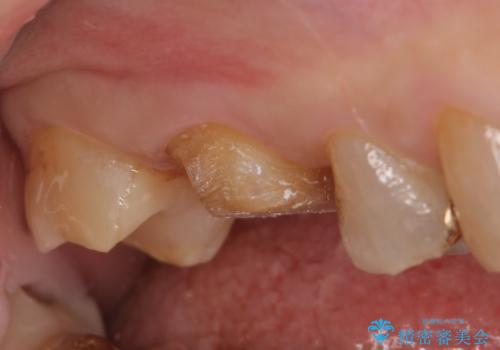

右上6,7の金歯を外したところ、虫歯が歯茎より深い位置まで進行していたため歯周外科を行いました。

その後歯茎の回復を待ち、オールセラミッククラウンおよびセラミックインレーによる補綴・修復を行いました。

虫歯が進み歯茎より深くなってしまうと、虫歯を取り残してしまうリスク、樹脂の硬化の妨げ、補綴物の不適合、歯肉炎・歯周病のリスクの増大等様々な弊害が起こり得ます。

そのため当院では歯周外科手術(歯茎を下げる手術)や歯の挺出による、虫歯が歯茎より深いという問題の解決を推奨しております。